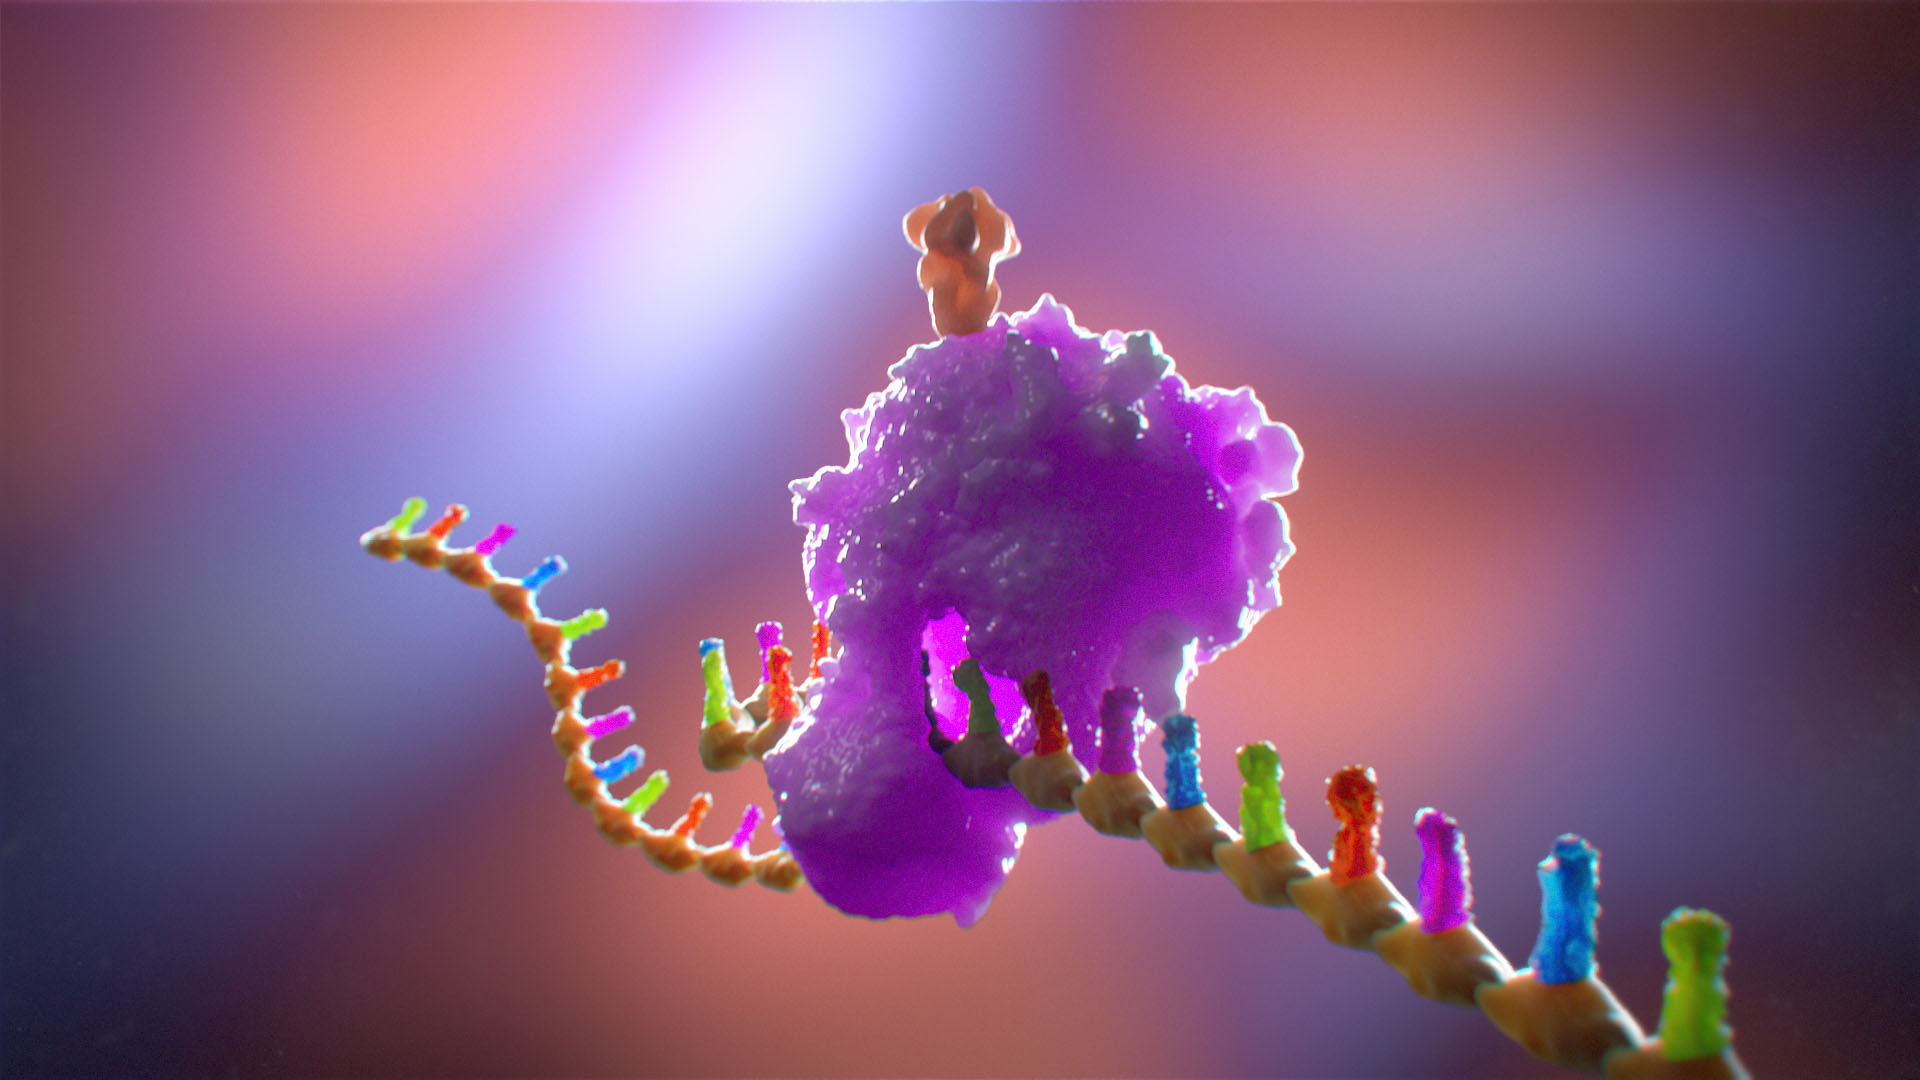

The world of medicine and healthcare is filled with complex concepts, intricate procedures, and marvels of human anatomy. Translating these intricate details into accessible and engaging visuals is no easy task. Ghost Medical Animation's team of animators and medical artists excel at merging the worlds of art and science, distilling complex medical information into eye-catching and informative illustrations.

With their keen eye for detail, the artists transform medical data, research findings, and clinical knowledge into visually appealing content. Each image and frame in their gallery serves as a bridge between the scientific realm and the general public, helping people comprehend medical concepts with ease while leaving them awe-inspired by the beauty of the human body's inner workings.

One of the most striking aspects of Ghost Medical Animation's Image Gallery is the diversity of subjects and medical fields covered. Whether it's depicting the intricacies of cellular biology, illustrating the intricacies of surgical techniques, or presenting the mechanism of action of pharmaceuticals, their artists are adept at handling a wide range of medical topics.

The team's expertise isn't limited to still medical illustrations; they are also masters of animation. They bring medical concepts to life through fluid and captivating animations, making it easier for both professionals and laypeople to understand complex medical processes. Through their skillful use of motion, the animations breathe life into scientific ideas, helping viewers envision dynamic physiological processes and medical advancements.